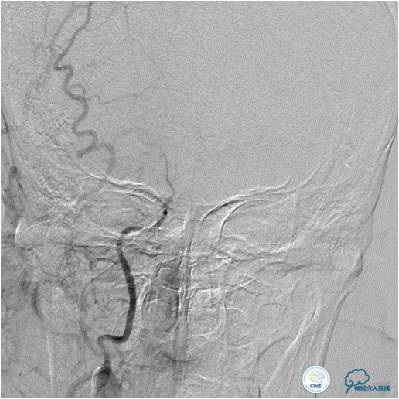

患者入院后,完善颅内CTA(图1)及血管造影(图2~3)检查,发现右侧颈内动脉颅内段闭塞,右侧大脑前动脉依靠左侧颈内动脉系统通过前交通动脉供血,右侧大脑中动脉供血区则依赖于右侧大脑前动脉(ACA)软脑膜代偿供血,左侧大脑中动脉闭塞,依靠一少见血管代偿供血,该血管起自左侧大脑前动脉A2段起始部,代偿供应左侧大脑中动脉供血区。由于该患者灌注CT(图4)未见明显低灌注区,遂给予患者抗血小板、降脂及控制危险因素治疗出院。出院后电话随访未再出现过上述症状。

图2:患者右侧颈内动脉造影提示右侧大脑中动脉次全闭塞,血流缓慢。大脑前动脉未见显影。